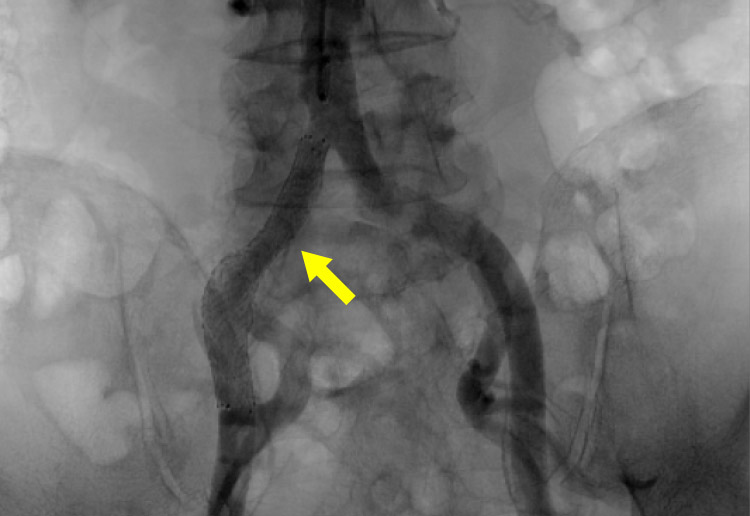

経皮的血管形成術(EVT)

狭くなった血管や詰まった血管に対して、カテーテルを使い、バルーンで拡張したり、ステント(金属の筒)を留置する治療を行います。石灰化が高度な病変には、バルーンだけでは拡張しにくいため、CROSSER(振動で石灰化を軟らかくする器具)を用いて治療することがあります。

閉塞している血管に対してワイヤーを通過させバルーン拡張し最終的にステントを留置し血管を拡げ、血流を改善します。